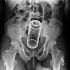

Quando o prazer vira um caso de emergência médica. Pessoas que se excederam e foram parar na emergência em função de objetos bizarros introduzidos no ânus. Confira.

Bala de Revólver